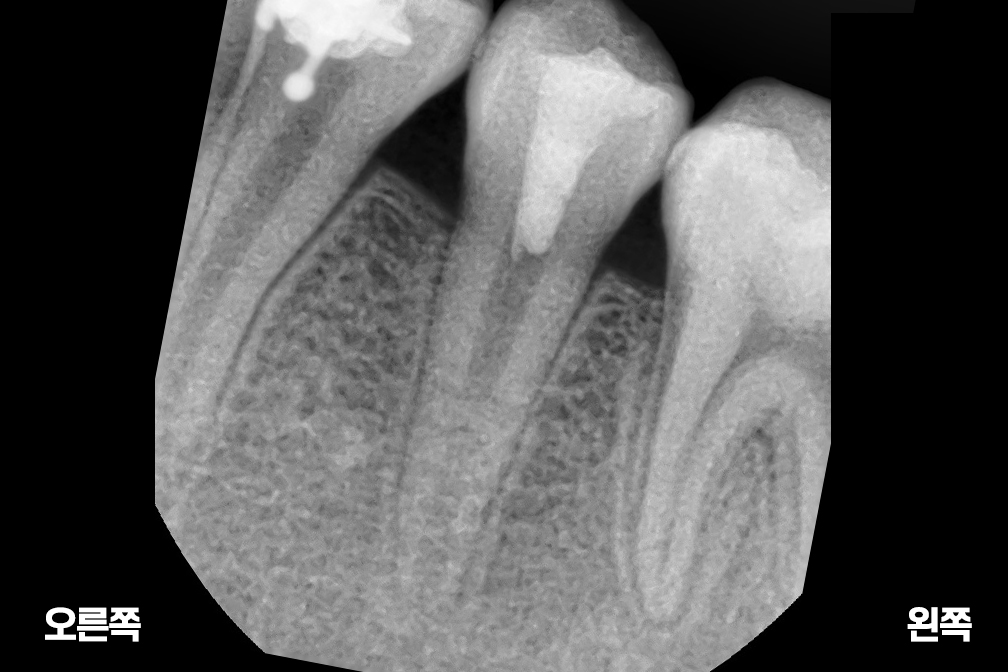

근관치료

Before 2025년 6월 25일